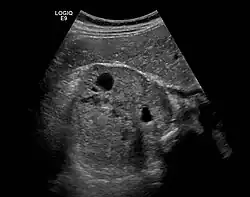

Das * markiert das Phäochromozytom.

Wenn die Bestimmung der Plasma-Metanephrine wiederholt ein positives Ergebnis bringt, muss eine weiterführende Lokalisationsdiagnostik durchgeführt werden. Dies geschieht mittels bildgebender Verfahren wie Computertomographie und Sonographie oder MRT-Bildgebung. Bei der CT ist zu berücksichtigen, dass beim Einlaufen von Jod-Kontrastmittel Katecholamine ausgeschüttet werden können, was bei der MRT nicht der Fall ist. Die nuklearmedizinische Methode der MIBG-Szintigrafie (Metaiodobenzylguanidin) dient vor allem dem Ausschluss von Phäochromozytomen außerhalb der Nebenniere. Diese Substanz lagert sich vornehmlich in den betroffenen chromaffinen Zellen des Phäochromozytoms ab. Die neueste und zuverlässigste Form der nuklearmedizinischen Methode ist bei Phäochromzytomen das so genannte DOPA-PET. Es wird zurzeit (Stand 2012) in Deutschland allerdings lediglich in wenigen Zentren angeboten. Zusätzlich muss auf alle Fälle nach Tumoren eines eventuellen MEN-Syndroms gesucht werden.